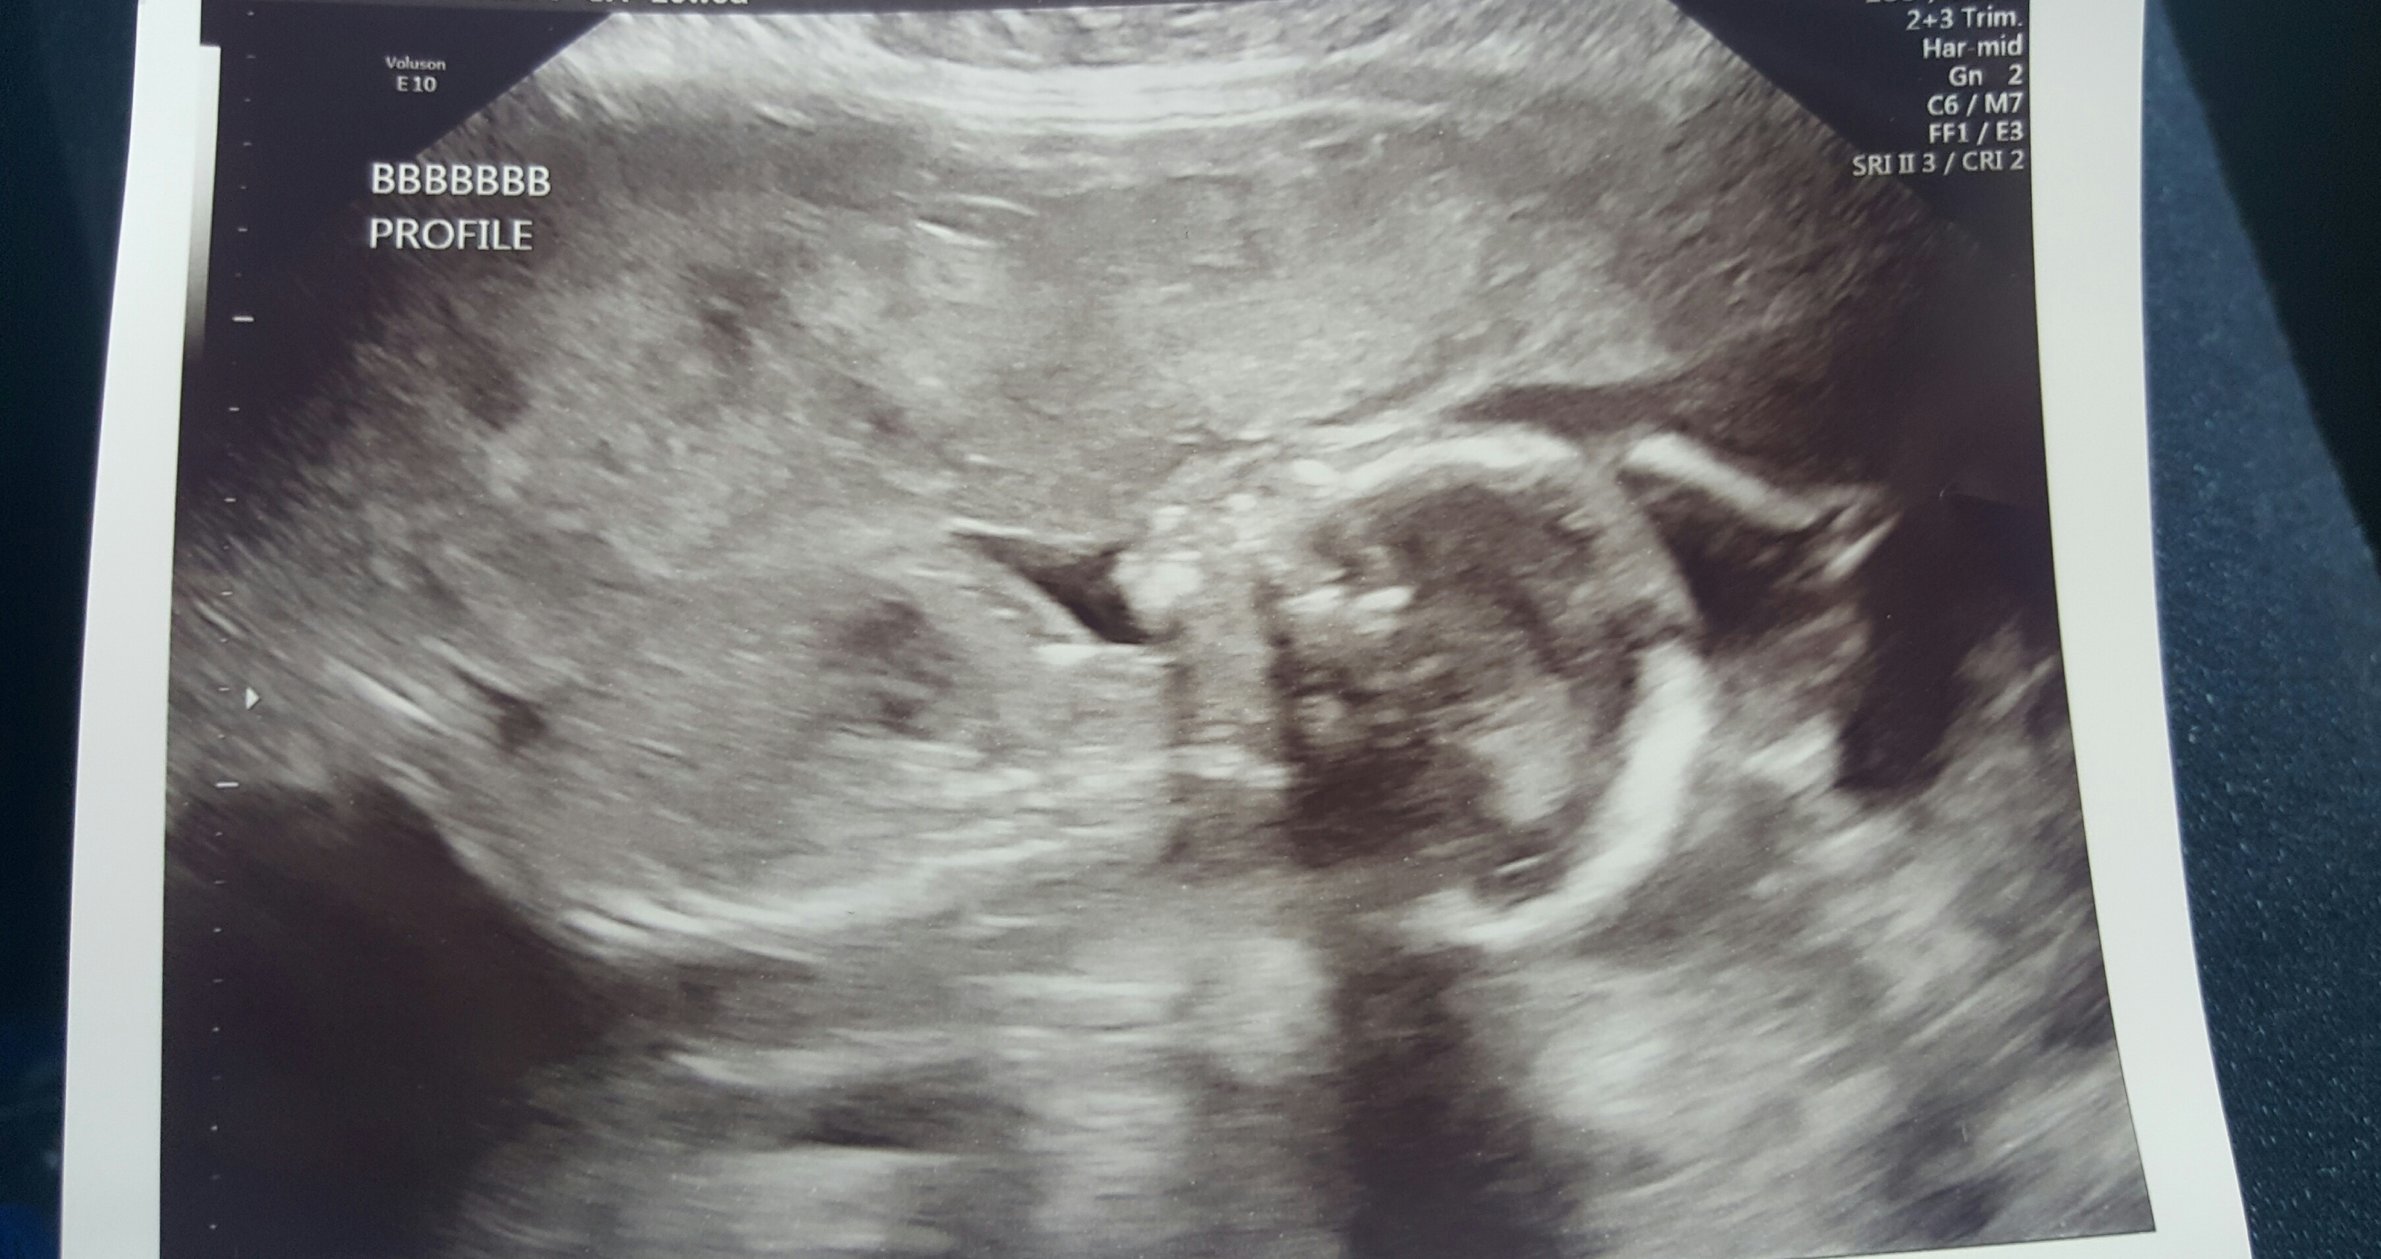

Re: Twin to Twin Transfusion Syndrome *TW*

BFP: 6/22/2016 EDD: 3/4/2017.